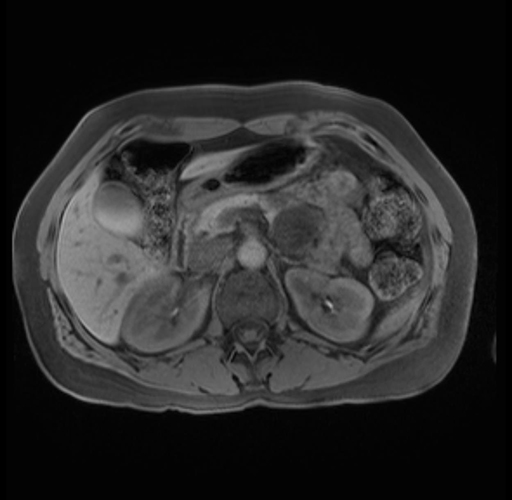

Imaging Analysis

Look through the patient's CT scan to identify any areas of concern for the necessary procedure.

Based on your CT findings, which issue(s) are present and would give reason for "planned slowing down moment(s)" in this case?